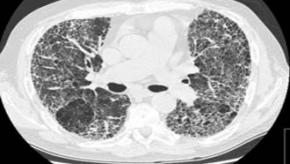

ILD and ANCA: What to do?

Several cohort studies conducted in Asia, Europe and the Americas have evaluated the clinical significance of antineutrophil cytoplasmic antibodies (ANCA) when detected in patients with interstitial lung disease (ILD) as well as the types of ILD encountered in patients with microsc